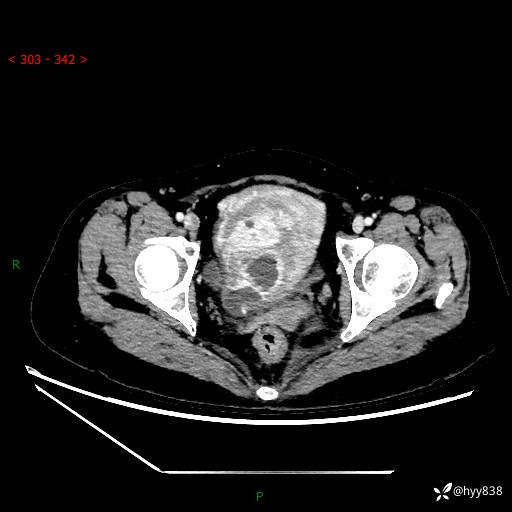

中老年女性,盆腔囊实性肿物,明显富血管强化,你懂得---结果公布~

简要病史:患者自然绝经2年。患者昨日于外院体检,行阴道彩超:盆腔内可见一约71*71mm无回声,形态欠规则,边界尚清,子宫附件显示不清。遂于今日来我院就诊,复查阴道彩超:子宫轮廓显示不清,大小约6.3cm×4.2cm×5.5cm,肌层回声欠均匀。CDFI:上述盆腔稍高回声内可见丰富血流信号。现患者无恶心呕吐、腹痛腹胀、阴道流液等症状,现患者为求进一步治疗,门诊以“盆腔占位”收入我科 起病以来,患者精神,食欲,睡眠好,二便正常,体力体重无异常改变。

临床诊断:盆腔肿物

盆腔CT平扫

增强(动脉期+静脉期)